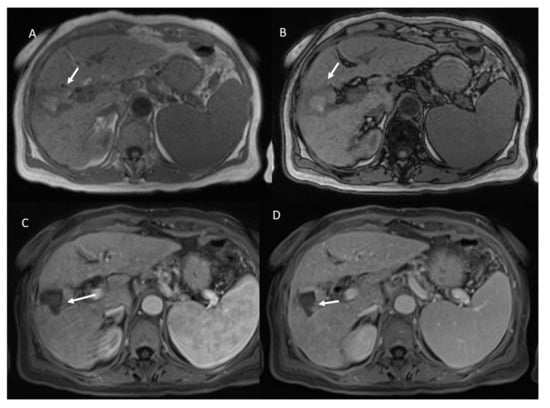

- 98 showed iso-hypointense SI in T2-W and 15 iso-hyperintense SI in T2-W (Figure 6).

- 100 showed hyperintense SI in T1-W and 113 targetoid appearance.

- 84 lesions showed restricted diffusion (Figure 7) with iso-hypointense in ADC map and 29 showed no restricted diffusion.